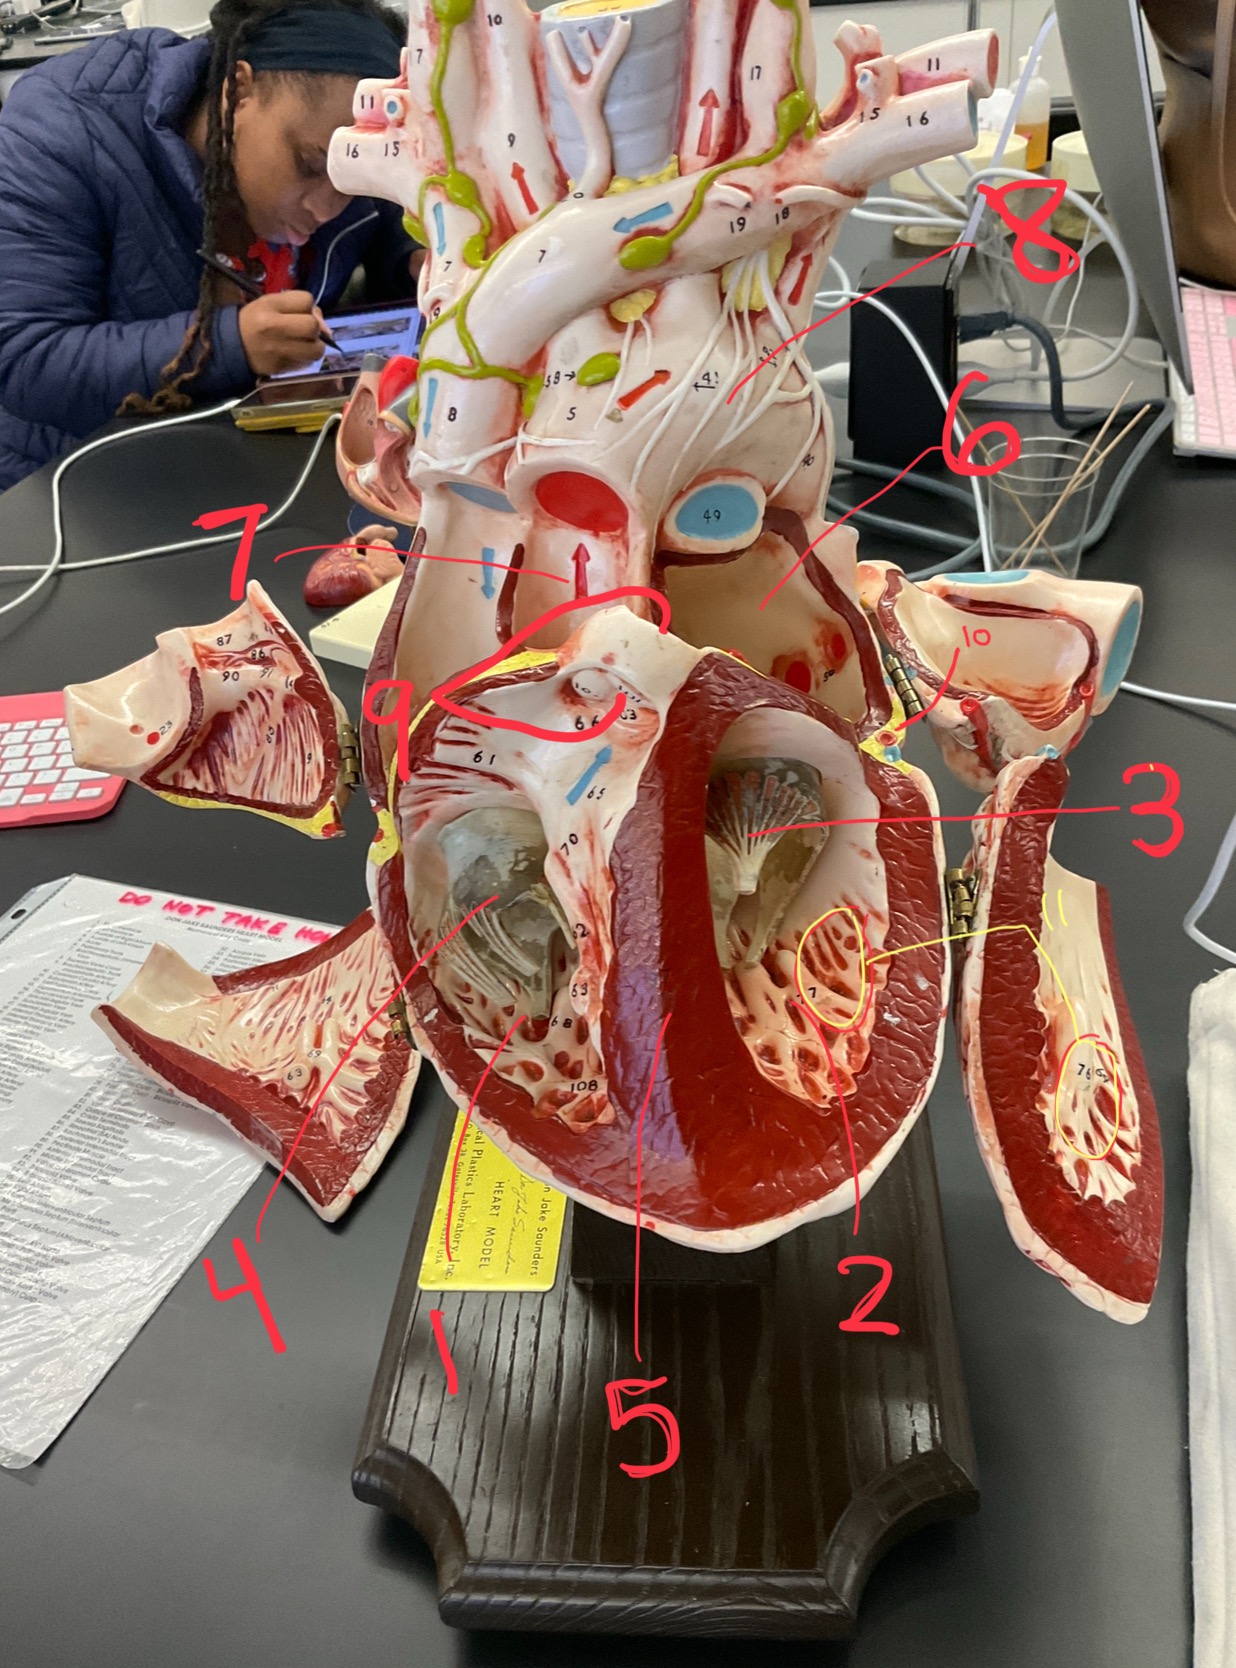

1

epicardium

2

3

endocardium

3

2

myocardium

4

1

coronary sinus

5

2

inferior vena cava

6

3

superior vena cava

7

1

right ventricle

8

2

left ventricle

9

3

bicuspid

10

4

tricuspid

11

5

interventricullar septum

12

6

left atrium

13

7

aorta

14

8

aortic trunk

15

9

pulmonary semi-lunar valve

16

10

atrevoventricullar sulus

17

11 (not smooth part)

trubeculae carneae

18

1

papillary muscle

19

2

chordae tendineae

20

4

pulmonary trunk

21

6

aortic trunk